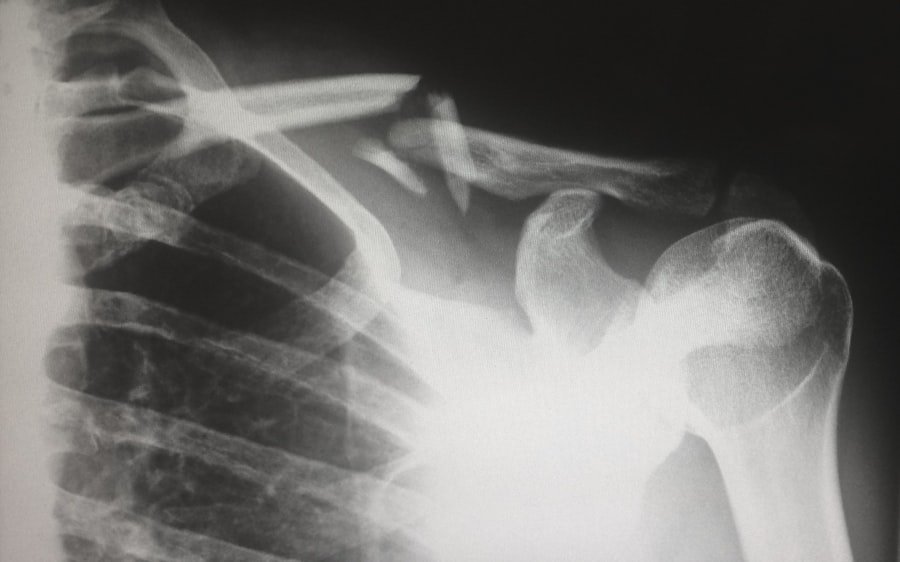

In some cases, imaging studies such as X-rays or MRI scans may be warranted to rule out other potential causes of upper back pain, such as herniated discs or structural abnormalities. These imaging techniques can provide valuable insights into the condition of surrounding tissues and help confirm a diagnosis of rhomboid muscle strain or injury. Ultimately, an accurate diagnosis is crucial for developing an effective treatment plan tailored to the individual’s specific needs.